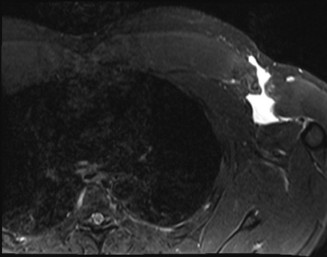

The correct answer is (B). An MRI showing a rotator cuff tear is considered diagnostic of a rotator cuff tear because of its high sensitivity, specificity, and accuracy. It has superb soft tissue imaging abilities (see Fig. 2–5). However, it should be noted that while MRI usually can differentiate between partial- and full-thickness rotator cuff tears, this varies with the power and accuracy of the MRI facility. This is also true with the ability of MRI to differentiate between partial-thickness rotator cuff tears and subacromial bursitis. An arthroscopy is needed for definitive differentiation of these pathologies.

Figure 2–5_Coronal oblique view MRI slice of a left shoulder. (Reproduced with permission from Smithius R and van de Woude HJ. Shoulder MR Anatomy: Normal Anatomy, Variants, and Checklist. _Radiology Assistant. April 2, 2012.)

MRI remains the most popular imaging modality for diagnosing rotator cuff tears. Normal rotator cuff tendon appears dark on both T1 and T2 sequences. Tears may be noted as being full-thickness, articular-sided, bursal-sided, or intrasubstance. They are visualized as a disruption in the regular contour of the tendon and increased signal intensity on T2 sequences. Occasionally, an MR arthrogram may provide additional information regarding a cuff tear, although this is not routinely ordered.

The correct answer is (D). T2 sequence causes most soft tissues, including muscle and tendon, to appear dark and inflammation, such as at the site of a tear, to appear bright. This means that if there is a rotator cuff tear, there will be a bright spot along the course of the dark rotator cuff tendon. This is easiest to pick out in the coronal plane because the tendon runs in this plane, allowing one to view the entire supraspinatus tendon and tear in one cut.